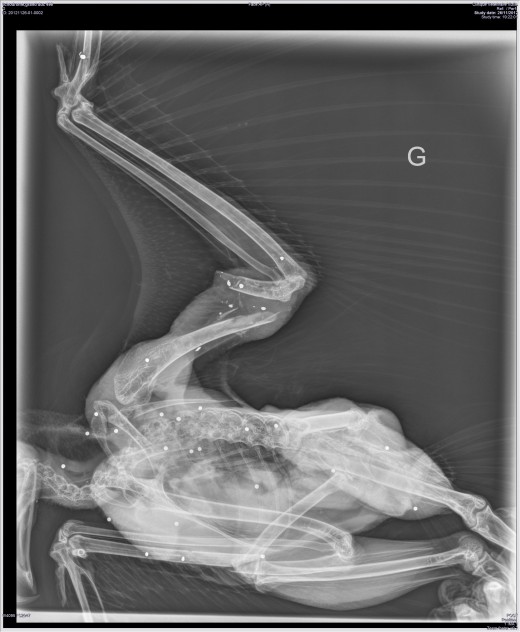

Le premier, opéré en urgence, n’a pas pu survivre. La radio révèle une vingtaine de plombs de petit calibre. Le tir a sans nul doute été effectué à courte distance. Le second a été retrouvé mort, criblé de 13 plombs de chasse. Les lois protégeant intégralement les rapaces tant nocturnes que diurnes sont pourtant anciennes. Elles visent à permettre la sauvegarde de ce patrimoine naturel qui autrefois était décimé. Ces espèces jouent un rôle primordial dans la conservation du patrimoine naturel er assure des servies inestimables à notre société notamment en régulant des espèces proies. La population nationale de Grand-duc se reconstitue progressivement : un réseau de 400 observateurs se mobilise pour connaitre l’évolution de l’espèce, proche de l’extinction dans les années 1960.